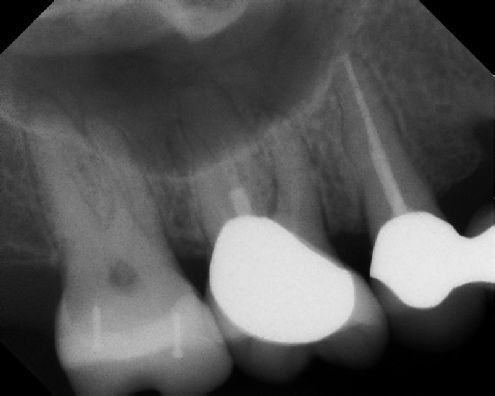

Root Canal Retreatment - Meriden 8 mos. recall Post-op Pre-op